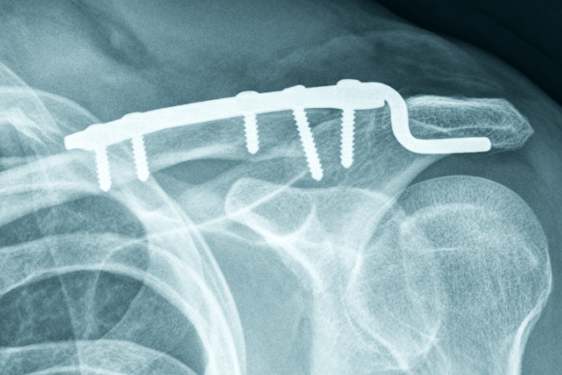

Plate Osteosynthesis

Plate osteosynthesis involves the use of metal plates and screws to stabilize fractures. This technique is commonly employed in fractures of long bones such as the femur, tibia, and humerus. The plate is positioned along the bone's surface, and screws are inserted through the plate and into the bone to secure it in place. Plate osteosynthesis provides rigid fixation, allowing for early mobilization and faster healing.